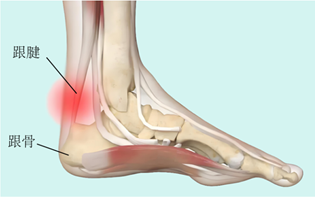

图1:跟腱的解剖示意图

图2:跟腱炎示意图